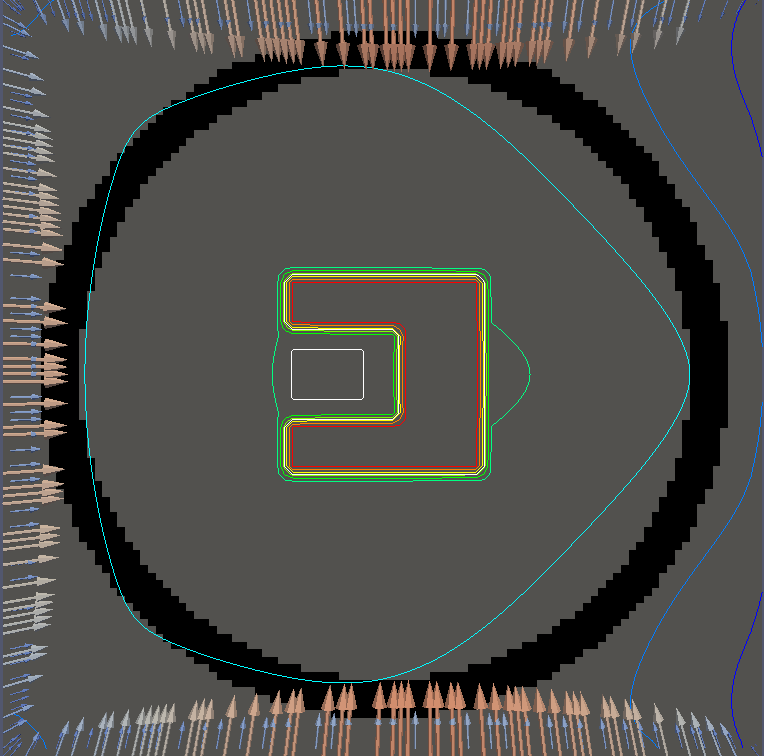

For testing, we use three tumor/risk region regions similar to those in [13]. Specifically, we define the regions in Table 3 and are shown in Figure 1; the void region is shown in black and the tumor and risk regions are traced in white. In the basic target case, seen in Figure 1(a), the tumor region is a box, as is the risk region. The second, intermediate target case, seen in Figure 1(b), involves an L-shaped tumor around a box-shaped risk region. Finally, the complex target case in Figure 1(c) involves a C-shaped tumor around a risk region.

Figure 2 shows the optimal boundary source term for both and The vectors shown on the boundary are the time-integrated values of normalized and then scaled by In Figures 2(a), 2(c), and 2(e) (corresponding to ), the isolines are spaced at intervals of the maximum of the desired dose (here, 5). In the intermediate and tracking cases, we see that relatively low dose levels are attained, primarily due to the high penalty to any dose deposited in the risk region. In Figures 2(b), 2(d), and 2(f)(corresponding to ), the isolines are spaced at intervals of of cells killed. Here a high proportion of the tumor cells are killed (in each case ) while in the Intermediate and Basic cases, the tumor has at least survival; in the Complex case, the risk region has survival.

We conclude with a final set of numerical examples which restrict the location of the source by altering the definition of Here we require that on one side of the boundary. For the basic and intermediate case, we require that the external source not come from the left side of For the complex case, we disallow sources on the right side (as the optimal source is nearly zero on the right side in the complex case for ). Figure 4 shows the optimal solution for both problems, using the same penalization parameters used in Figure 2. The optimal dose for is significantly worse, with the tumor in the intermediate and complex cases getting a dose below However, the tumor cells have a survival of or less for each case and the risk region has a survival rate of or higher in each case.